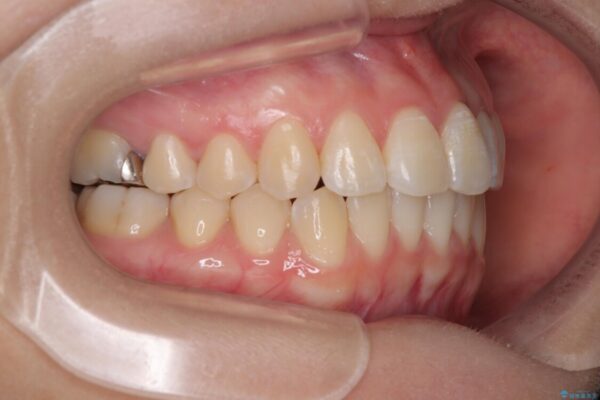

診察の結果、上下の前歯部に**叢生(そうせい/歯のガタガタ・重なり)**が認められました。

特に上の前歯にはねじれや重なりがあり、審美的にも清掃性にも影響している状態でした。

治療前

• 前歯のねじれ・ガタガタを10か月で改善!20代女性の矯正治療|クリアブラケットでむし歯になりにくい歯並びへ改善 治療前画像